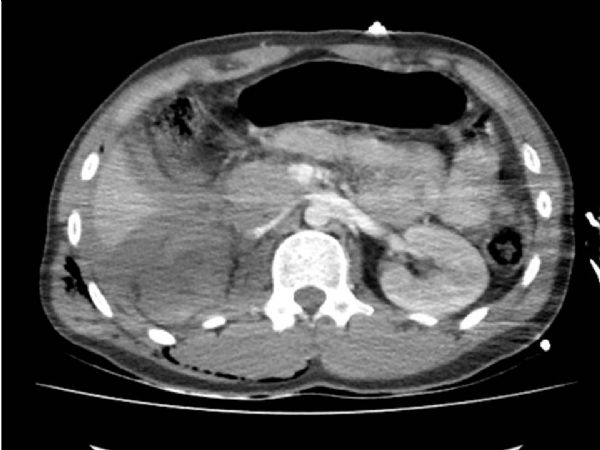

YÖNTEM: Yirmi iki yaşında erkek hasta AİTK nedeniyle acil servise getirildi. Hastanın ilk değerlendirmesinde genel durumunun kötü, şurunun kapalı olduğu gözlendi TA:40/50 mm/Hg Nabız:109/dk. idi. Laboratuarında Hb/Htc: 11/36 olup yapılan kontrastlı tüm vücut tomografisinde sağ böbreğin kontrast tutmaması dışında özellik yoktu. Böbrek konturları normal olarak gözlendi (Resim 1). Vital bulguları stabil olmayan hasta bu bulgular ile acil şartlarda operasyona alındı.

METHOD: Twenty-two year old male patient was brought to the emergency department because of ICTA. In the initial assessment: the patient's general condition was bad, and unconsciousness. Blood pressure (BP) was 40/50 mm/Hg and heart rate (HR) was 109/min. Laboratory Hb / Hct: 11/36 and the whole-body CT scan with contrast was unremarkable except right kidney was not contrast enhancement. Normal renal contour was observed (Figure 1). The patient was operated under emergency condition with unstabil vital signs and this findings.

Resim 1

Figure 1